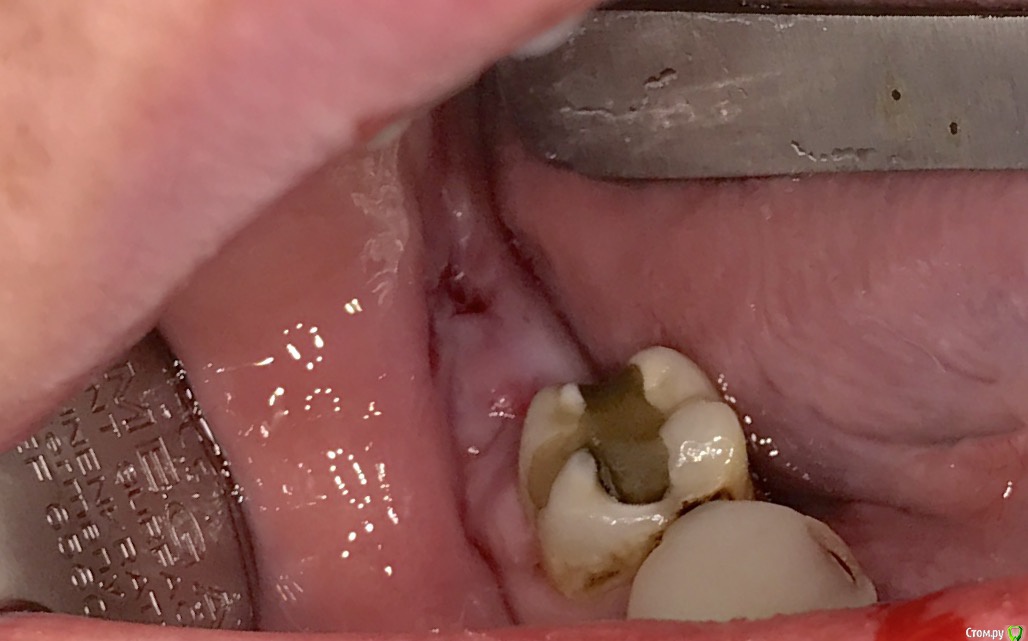

колесников Опубликовано 25 марта, 2017 Автор Поделиться Опубликовано 25 марта, 2017 Повторение-мать учения 1 Ссылка на комментарий

Irouil Опубликовано 25 марта, 2017 Поделиться Опубликовано 25 марта, 2017 Это язычный? Ссылка на комментарий

колесников Опубликовано 25 марта, 2017 Автор Поделиться Опубликовано 25 марта, 2017 Он Ссылка на комментарий